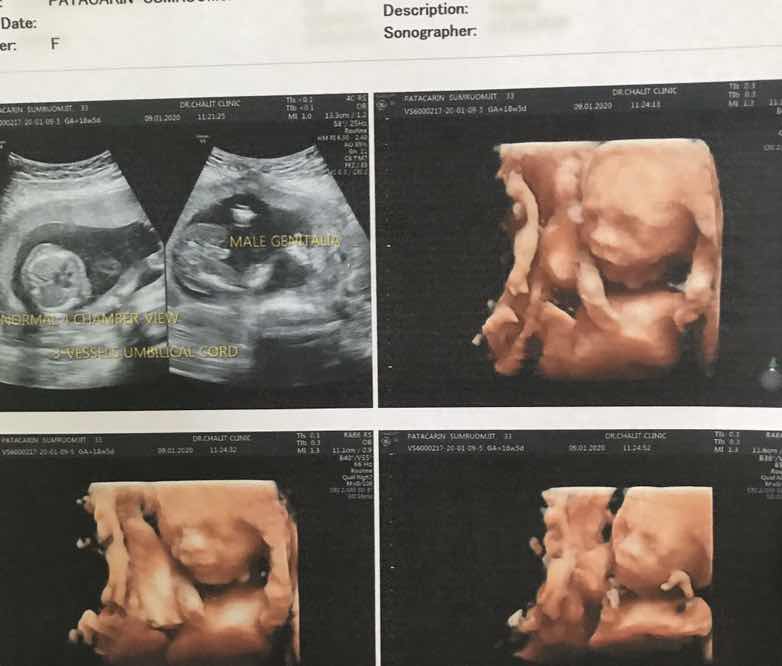

กำหนดคลอดเดือนมิถุนายนตอนนี้ซาวด์จะเห็นเพศกันรึยังคะ บ้านนี้ลุ้นหนักมากเลยค่ะ

6 มิย ผมเป็นผุ้ชายครับ